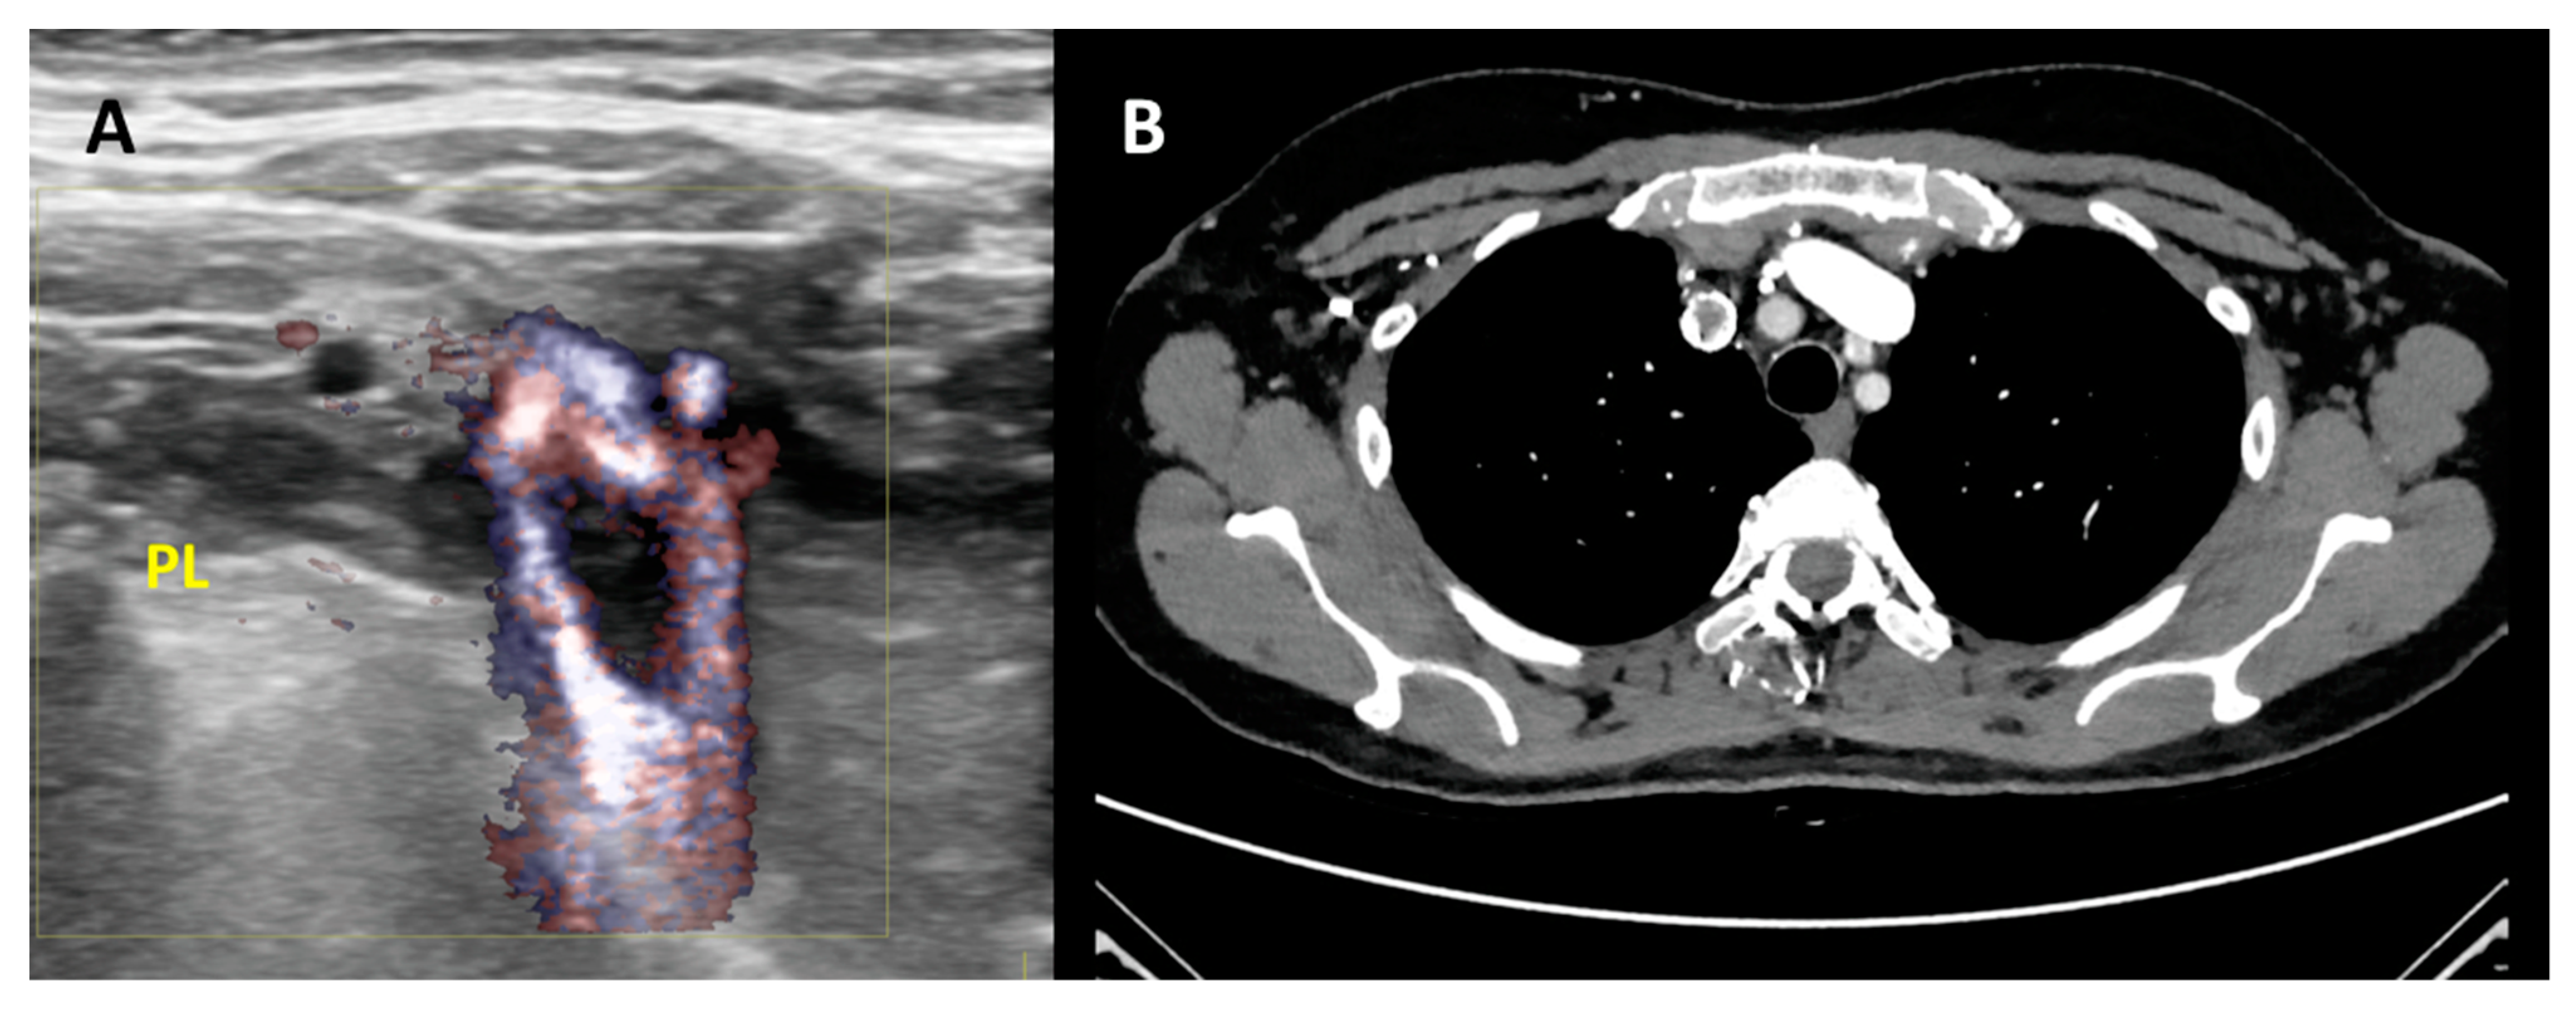

3.11. Second Level Diagnosis

- Zamboni, P.; Scerrati, A.; Menegatti, E.; Galeotti, R.; Lapparelli, M.; Traina, L.; Tessari, M.; Ciorba, A.; De Bonis, P.; Pelucchi, S. The eagle jugular syndrome. BMC Neurol. 2019, 19, 333. [Google Scholar] [CrossRef] [PubMed] [Green Version]